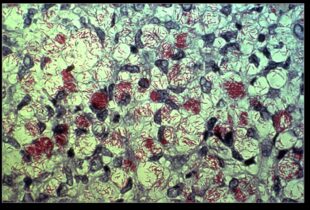

Lepra ili guba je kronična zarazna bolest koju uzrokuje acidorezistentni, štapićasti bacil Mycobacterium leprae. Naziva se još i guba te...